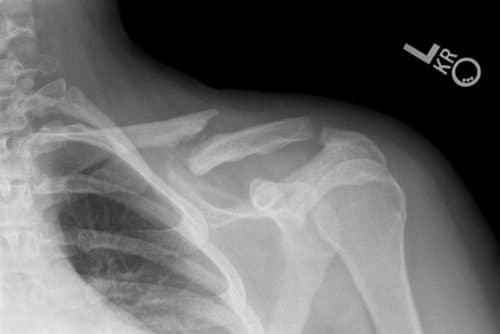

Gãy Xương Đòn Trường Hợp Nào Cần phẫu thuật & Phải Mổ?

Xương đòn hay còn gọi là xương quai xanh, xương dẹt cong hình chữ S, một đầu tiếp với xương ức và một đầu tiếp giáp với xương bả vai. Xương đòn thường bị gãy trong các trường hợp tai nạn, chấn thương do va đập mạnh ở vùng bả vai. Vậy gãy xương đòn […]